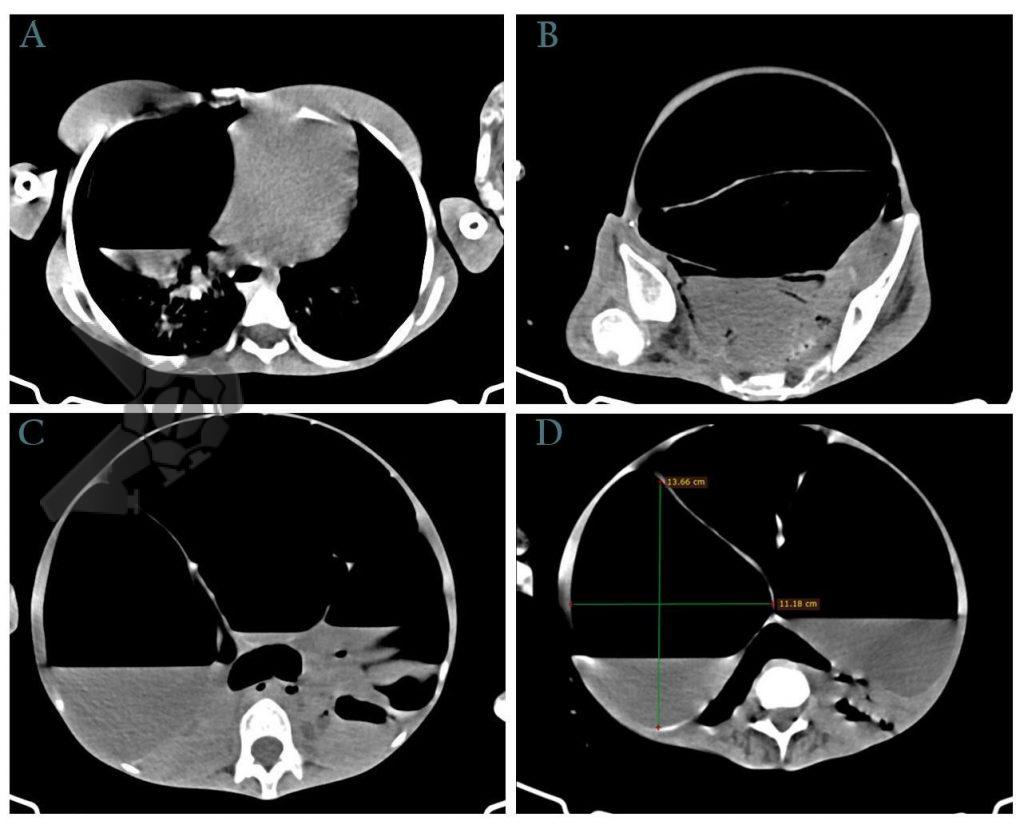

Masculino, 88 anos, aposentado, apresentando quadro demencial leve, assintomático, foi encaminhado ao serviço de endoscopia após a ingestão acidental de sua prótese dentária fixa. O incidente ocorreu há 15 dias, sem eliminação do objeto nas fezes desde então. Ele buscou atendimento na unidade de emergência de sua cidade, onde uma radiografia revelou a presença do objeto na topografia da fossa ilíaca direita (foto 1). Ao exame físico, não havia alterações relevantes com palpação do abdome inocente.

Após preparo colônico com manitol e a realização de uma nova radiografia, que não apontou qualquer mudança na posição inicial da prótese dentária desde a admissão, o paciente foi submetido a colonoscopia. Até a intubação cecal o corpo estranho não foi encontrado, com presença de doença diverticular no hemicólon esquerdo (foto 2 e 3).

Avaliar as características do corpo estranho ingerido como sua forma, quantidade, tamanho, superfície, consistência, mobilidade, entre outros, é crucial ao considerar a remoção colonoscópica, a fim de traçar uma estratégia terapêutica e prever possíveis complicações. Esse risco aumenta consideravelmente quando o objeto é alongado e possui uma superfície pontiaguda, como espinhas de peixe, ossos de galinha ou palitos de dente. Há uma variedade de dispositivos disponíveis para auxiliar a extração, e a escolha deve ser feita após análise minuciosa das peculiaridades do corpo estranho. Estes dispositivos incluem CAPs (rígidos, flexíveis, plásticos, de látex), alças e pinças de diferentes tamanhos e formatos, rede coletora (Roth Net), overtube, fio guia, entre outros. A radiografia e a tomografia de abdome são importantes para definir o posicionamento do CE ao longo do TGI, se possível, deve ser realizado antes e após o preparo do cólon, para se certificar que não houve mudança do posicionamento do objeto.